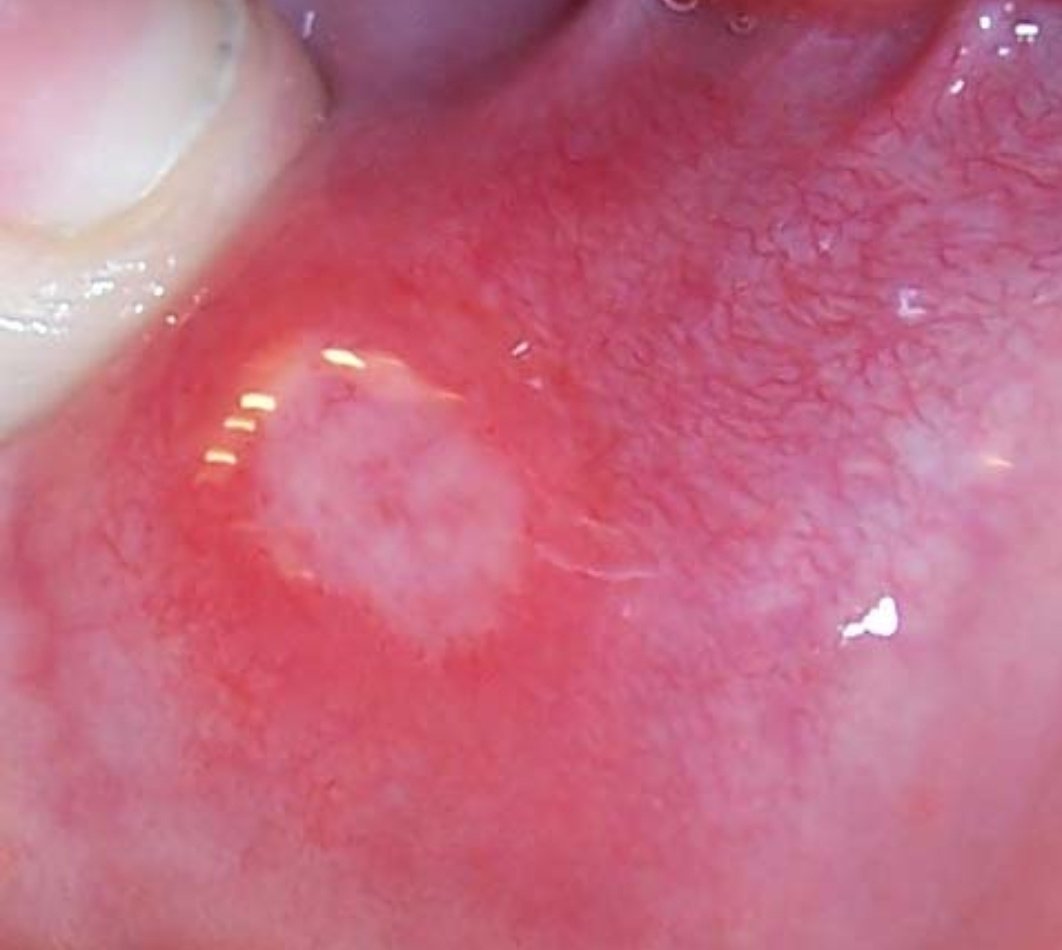

القرح القلاعية (Oral aphthous)

هي تقرحات مؤلمة متكررة، تكون منفردة او متعددة من ناحية الكم. هناك نوعان من القرح النوع الصغير (عدة مليمترات) الأكثر شيوعاً

والنوع الكبير (اكبر من نصف سنتيمتر) #مع_دكتور_عصام

تلتئم القروح الصغيرة في غضون أسبوع تقريبًا و القروح الكبيرة قد يستغرق الشفاء عدة أسابيع. لا يوجد علاج أو علاج موضعي ثبت أنه له تأثير على الشفاء أو على الوقاية من القروح.